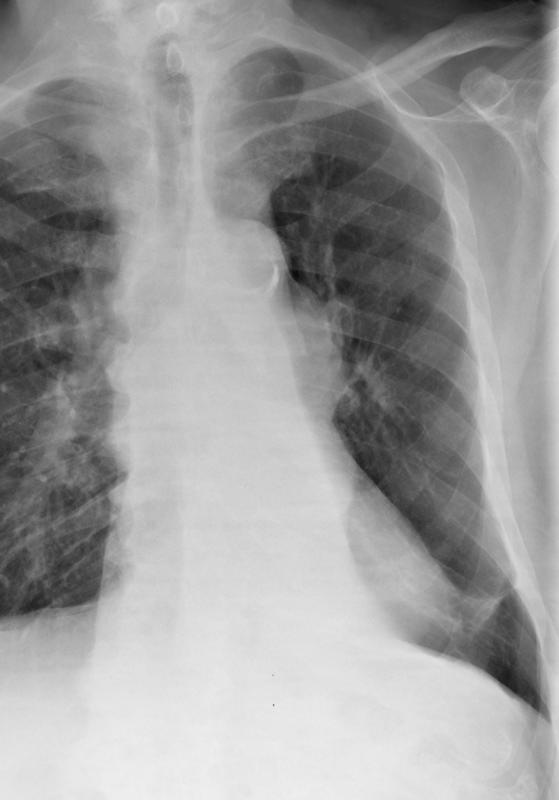

LLL collapse

Hilar mass  Case 10